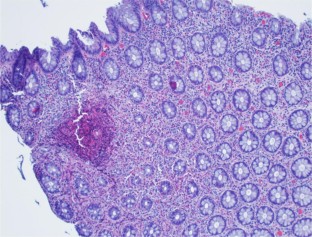

Fig. 1